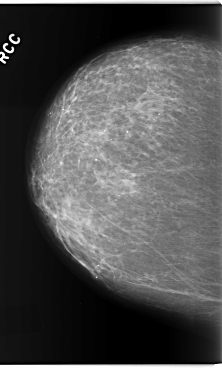

C_0205_1.RIGHT_MLO

RIGHT_CC LINES 5888 PIXELS_PER_LINE 3552 BITS_PER_PIXEL 12 RESOLUTION 50 NON_OVERLAY

RIGHT_MLO LINES 5880 PIXELS_PER_LINE 3936 BITS_PER_PIXEL 12 RESOLUTION 50 NON_OVERLAY